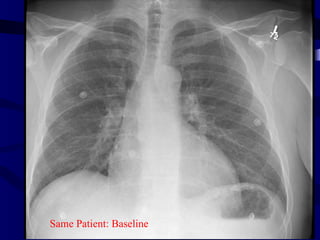

Same Patient

baseline

Same Patient: Baseline